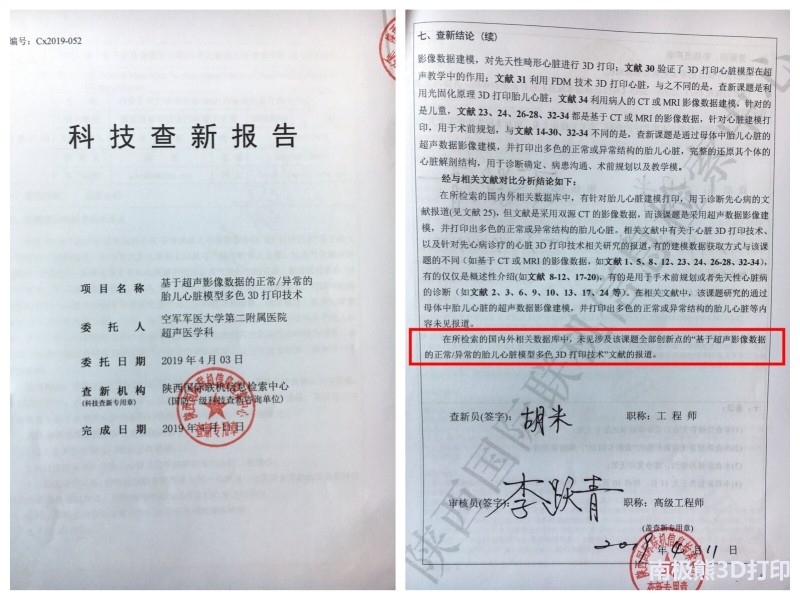

经陕西国际联机信息检索中心查新,该技术属于世界首例。